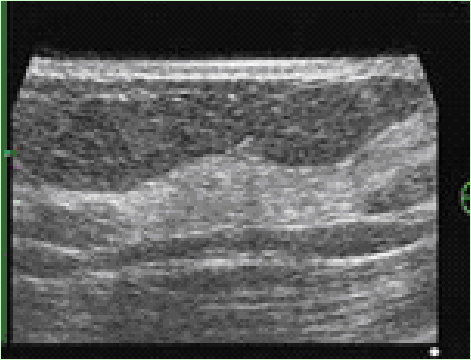

正常乳腺は皮下脂肪組織内に白い部分として描出されます。一般に表面から表皮層、浅在筋膜浅層の白い線が描出され、そこからクーパー靭帯によって吊り下げられるように乳腺が存在します。

後方では浅在筋膜深層と大胸筋が黒く描出されます。

乳腺のしこりの超音波画像